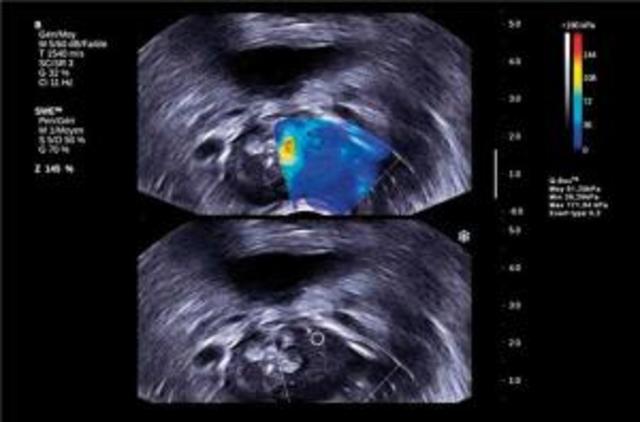

• Invention of the Detection method elastography

Invention of the Detection method elastography

New detection method, Norway and France were the first to use it. The method measures the elasticity of the tumors.